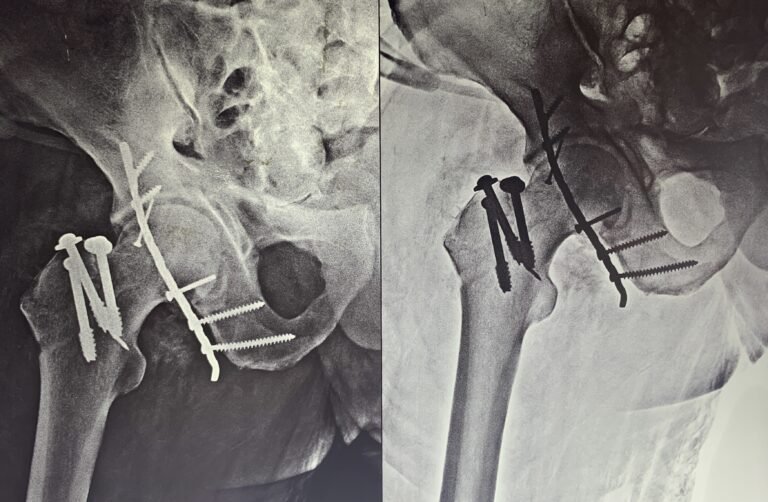

Dr. Tripathi specializes in the intricate field of pelvic and acetabular surgery, a branch of orthopedics dealing with complex fractures and injuries of the pelvic girdle and hip socket. His extensive training and experience enable him to handle the most challenging cases with precision and care. He is adept at both surgical and non-surgical management of these conditions, ensuring comprehensive care tailored to each patient’s needs.